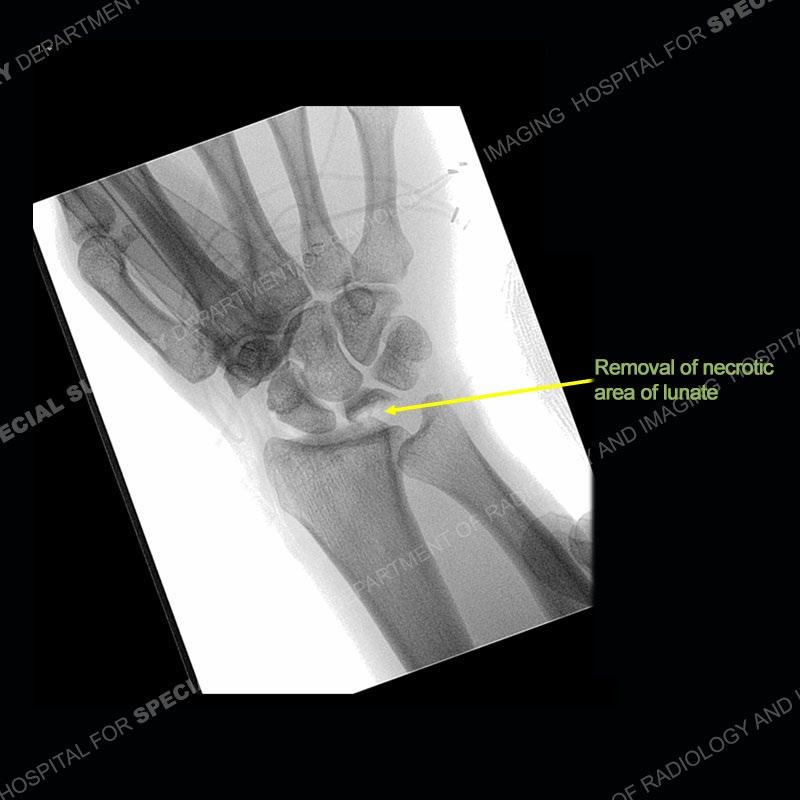

The treatment as the underlying cause of Kienbock’s remains somewhat elusive. Prior to collapse, osteotomies to decrease load or shearing forces to the lunate may be helpful. Once collapse and arthritis have been engendered, fusion and carpectomy have been performed. Now, the role for vascularized bone grafting is being investigated with long term results still being somewhat lacking. Given the young age of the second patient and lack of adjacent, advanced cartilage wear, a vascularized bone graft was performed. The area of necrotic bone was excised, a vascularized bone graft from the distal femur was harvested, and then using microsurgical technique it was grafted to the lunate. A temporary fixation was performed and once the graft was incorporated, the fixation hardware was removed. Although still early in the postoperative period, the patient is doing well.